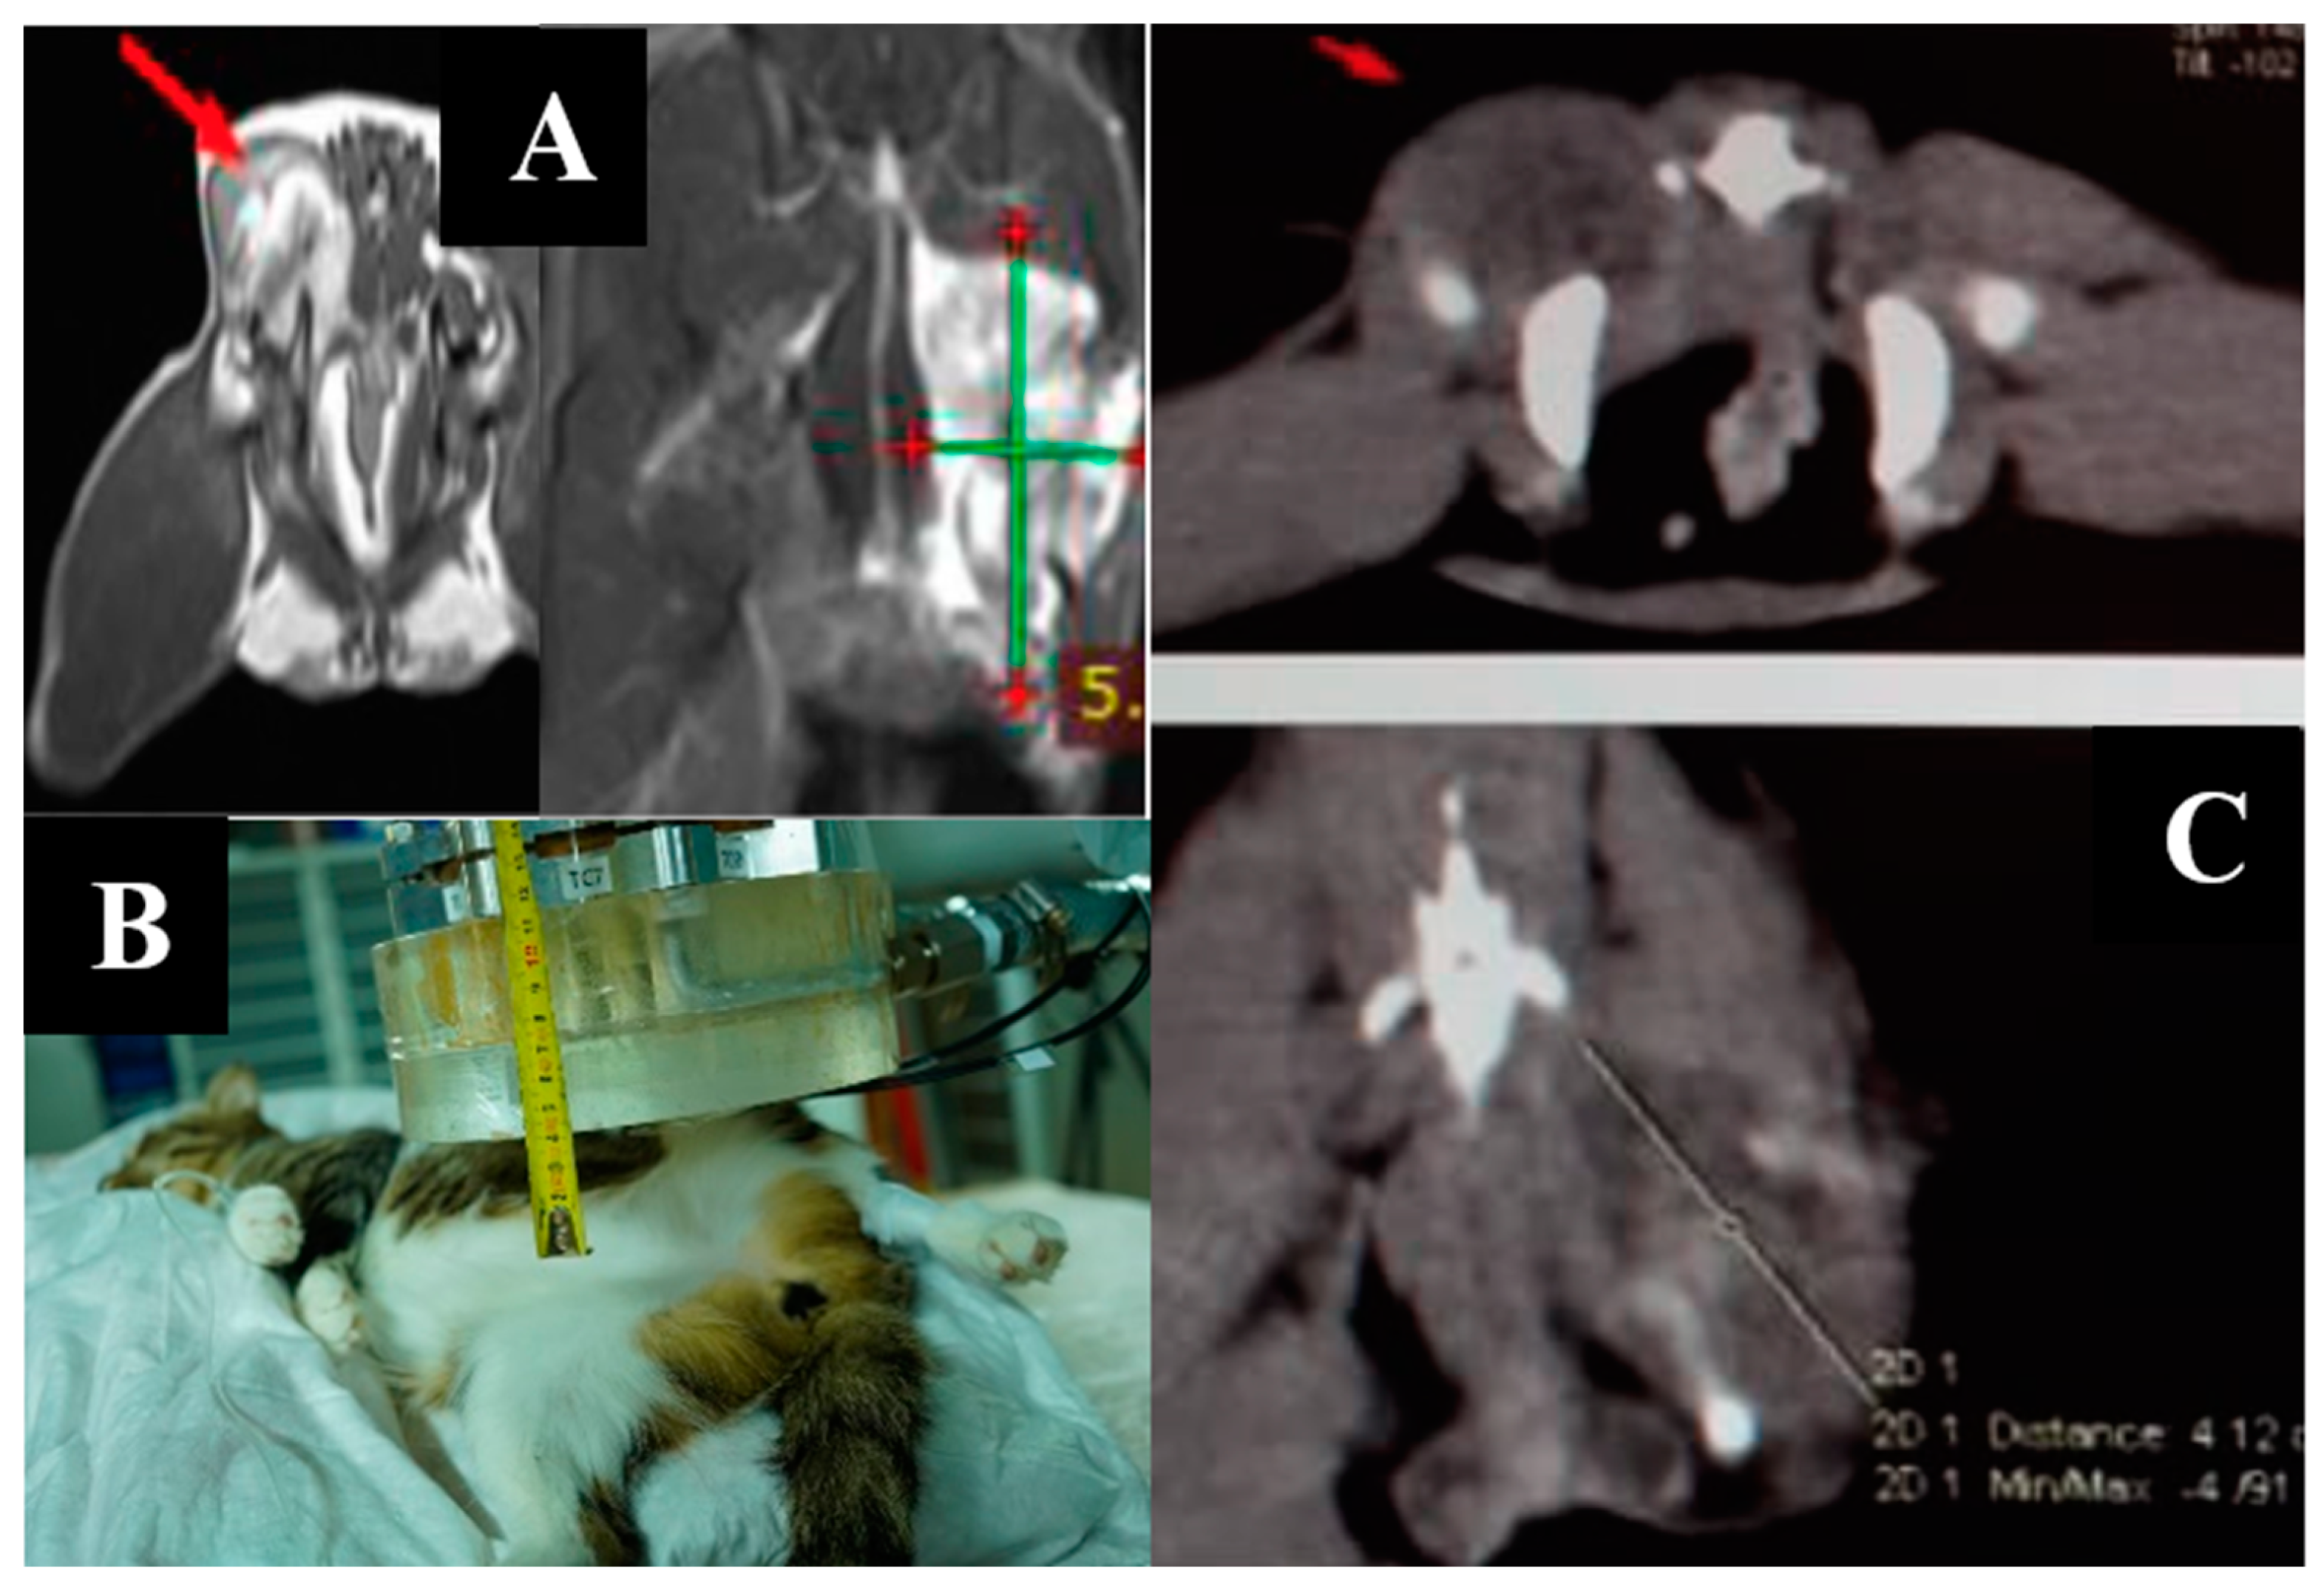

3.8. Case 8

3.9. Case 9

4. Discussion